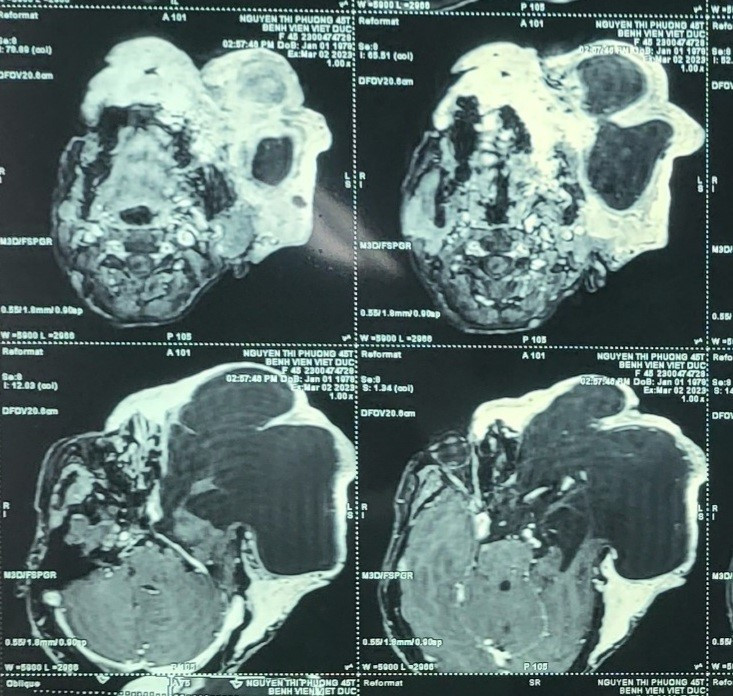

PGS.TS Nguyễn Hồng Hà, Trưởng khoa Phẫu thuật Hàm mặt - Tạo hình - Thẩm mỹ, Bệnh viện Hữu nghị Việt Đức, cho biết người bệnh bị u xơ thần kinh khổng lồ vùng đầu mặt trái.

Khối u bẩm sinh phát triển rầm rộ ra bên ngoài, làm tiêu phần lớn xương cánh bướm của hộp sọ và ổ mắt. Một phần lớn khối u từ não phát triển ra ngoài làm cho nhãn cầu rơi ra khỏi ổ mắt, khối u thông trực tiếp với não bộ.

"Do đặc thù của loại u khổng lồ được cấp máu bằng loạt hệ thống mạch máu chằng chịt trong và ngoài sọ, khiến khối u luôn đập theo nhịp mạch và nóng hơn các vùng khác trên cơ thể 1 đến 2 độ C", bác sĩ Hà cho biết. Điều này làm khả năng điều trị rất khó. Khi phẫu thuật tiềm ẩn nguy cơ chảy máu chết người ngay trong mổ hoặc viêm màng não, dò dịch não tủy nhiễm trùng nặng sau mổ.